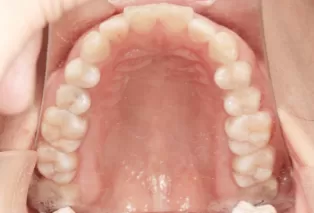

Photos intra-orales